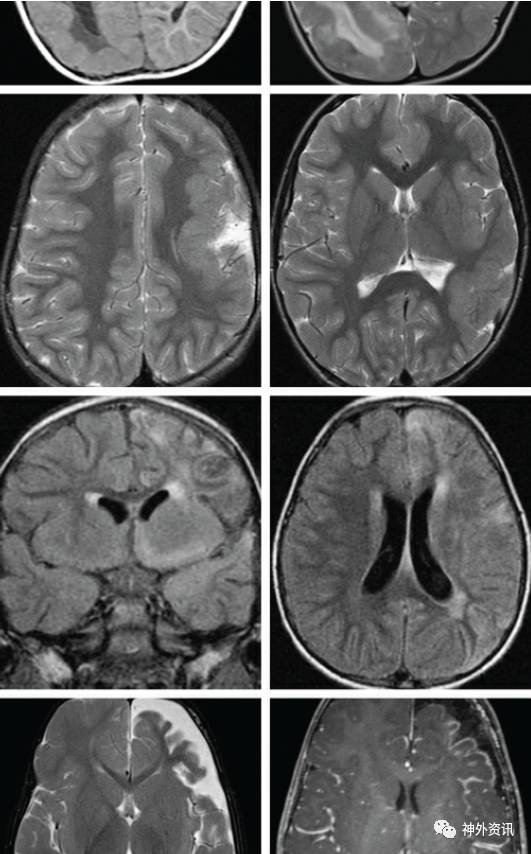

图1. 显示为右侧中等程度的半侧巨脑症。弥散性的皮层发育异常(最上图);注意脑室周围的变化;异位的灰质被发现在脑室周围;这些异常的变化在后半球尤为明显。第二排图显示:左侧外侧裂周围区的脑回增厚。第三排图显示与左侧相符合的Rasmussen’s脑炎的影像学表现,同时为手术活检证实;T2相显示异常者为脑组织的萎缩。最下图显示了Sturge-Weber综合征的影像学表现:左侧额颞叶的萎缩、枕叶软脑膜的增厚和枕极增强表现,提示血管病变。